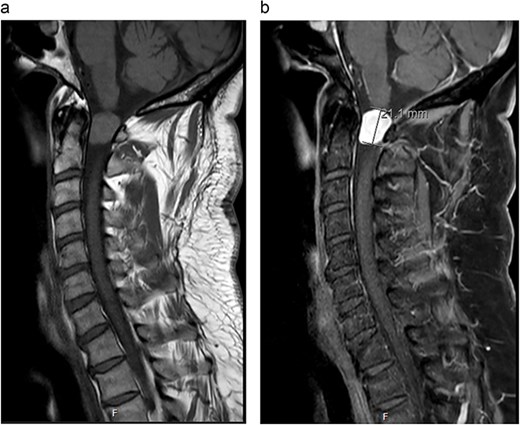

MRI cervical spine (Fig. 1) demonstrated an extramedullary intradural lesion at C1/2 within the right aspect of the canal distorting and compressing the cord to the left with associated cord signal changes. The lesion is isointense on T1- and T2-weighted images and measures ~1.7 × 2.0 × 2.1 cm. Following contrast (Fig. 2), there is homogenous enhancement of the lesion. Computed tomography of thorax, abdomen, and pelvis showed no evidence of primary lesions or skeletal deposits.

(a) Pre-operative sagittal MRI cervical spine T1-weighted image without contrast. (b) Pre-operative sagittal MRI cervical spine T1-weighted image with contrast.